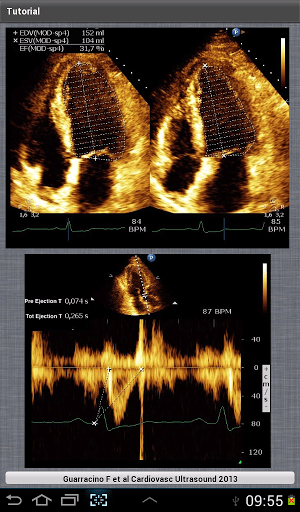

iElastance: Calculates Ventricular Elastance, Arterial Elastance and Ventricular-Arterial Coupling using Echocardiographic derived values in a single beat determination

Reporter: Aviva Lev-Ari, PhD, RN

First iElastance release for Android!

iElastance is an application designed for calculate Ventricular Elastance, Arterial Elastance and Ventricular-Arterial Coupling using Echocardiographic derived values in a single beat determination.

This application is extremely useful to a variety of health care givers such as Cardiologists, Intensivists, Anesthesiologist and more who want to calculate ventricular arterial coupling even in the Critical Care setting and, above all, bedside.

The variables needed for the calculator to work are:

Systolic Blood Pressure (mmHg)